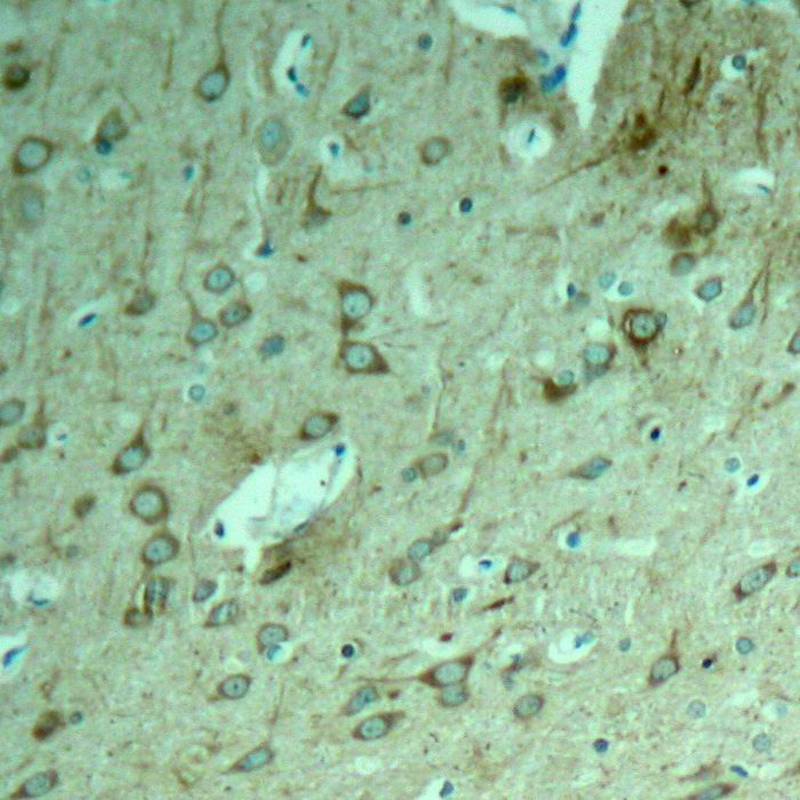

分类: 科研抗体货号: P41321别名: Neurofibrillary tangle protein; Paired helical filament-tau;应用: WB,IHC反应种属: Human,Mouse,Rat